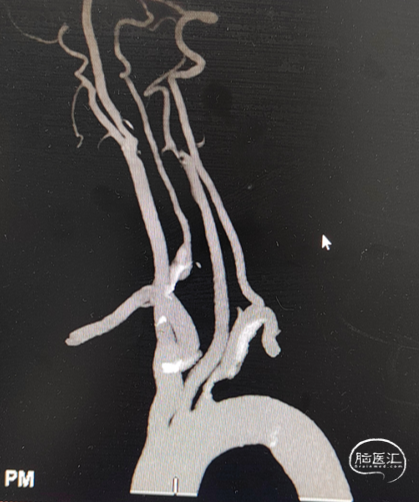

头颈部CTA影像及报告(2024-07-24)。

入院头颈部CTA影像及报告(2024-09-05)。